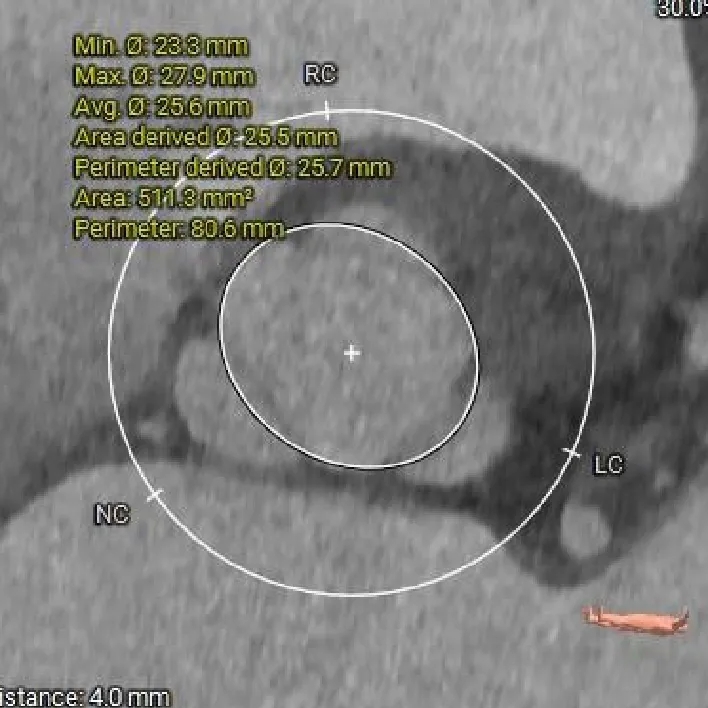

主动脉根部测量

Annulus

25.9mm

瓣上结构测量

瓣上2mm

25.7mm

瓣上4mm

瓣上6mm

26.2mm

瓣上8mm

27.3mm

-

瓣上锚定空间逐渐增大